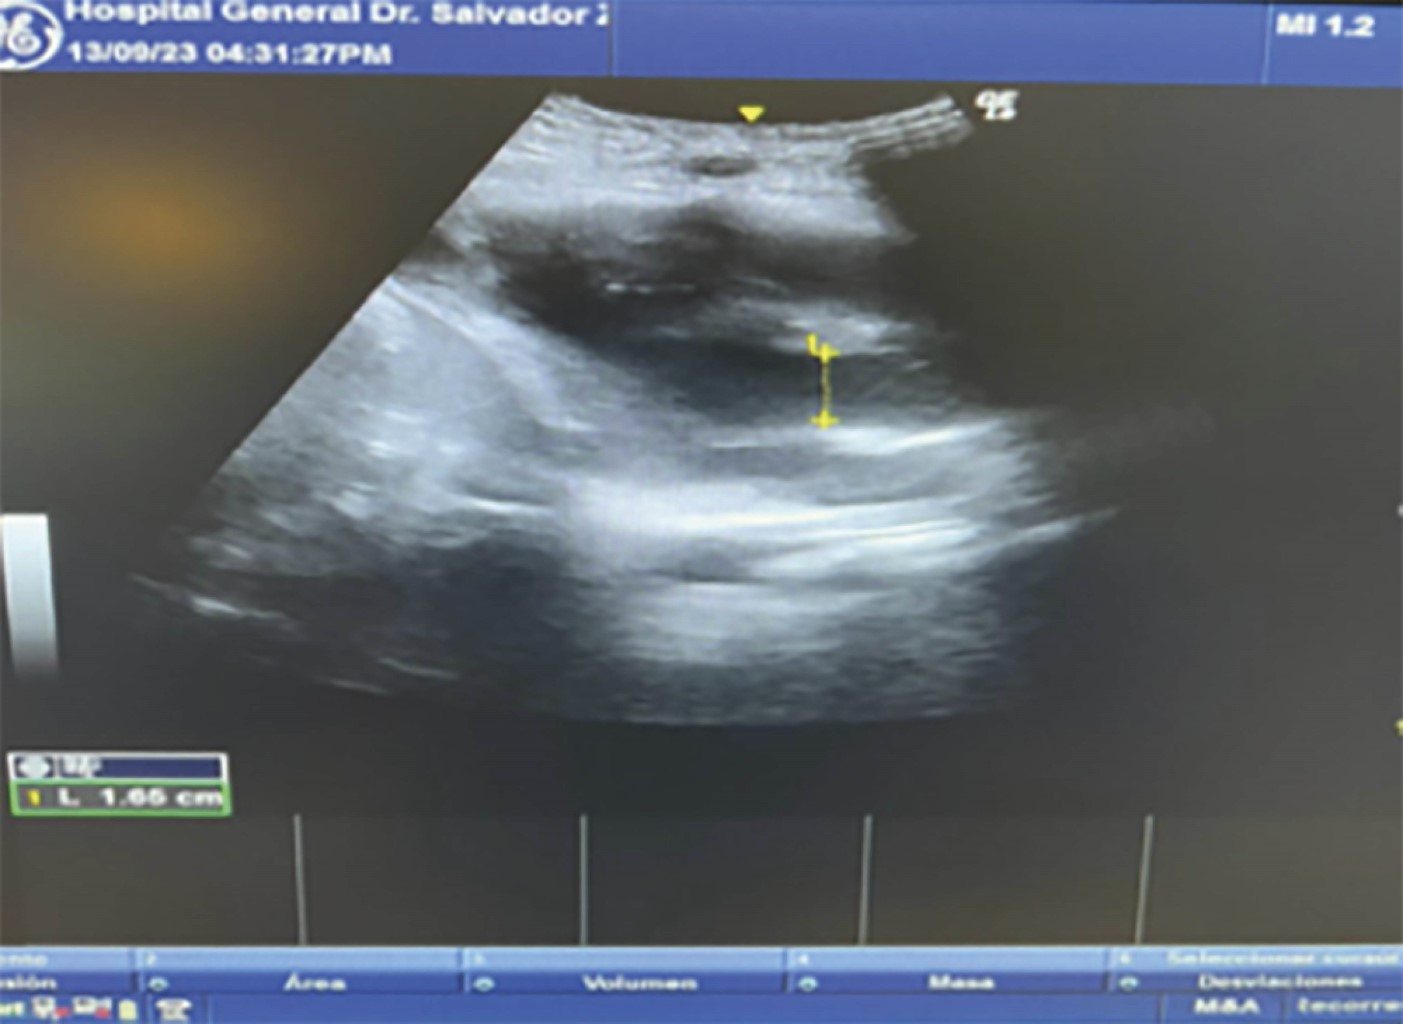

Durante su evolución, se evidencia deterioro hemodinámico con aumento de requerimiento de vasopresores con disminución de SvO2, en la ecocardioscopia se observa hipocinesia del ventrículo izquierdo con una integral velocidad tiempo de 11.1 cm/s, y diámetro de tracto de salida del ventrículo izquierdo de 1.65 cm, con gasto cardiaco de 2.38 L/min (Figura 1 y 2) como deterioro del estado ácido-base con presencia de acidosis metabólica de anión gap elevado (Tabla 3) concomitante con acidosis metabólica de anión gap normal.

Figura 1